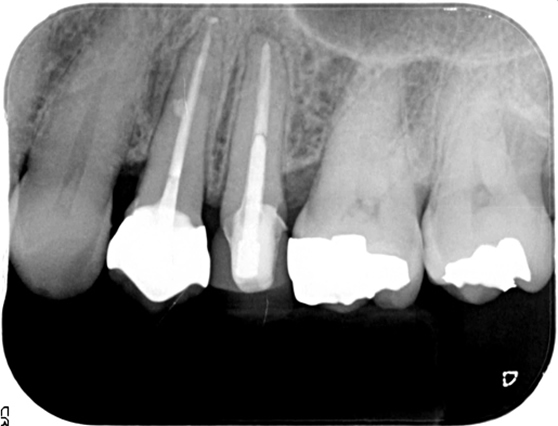

左上の5番が再治療しても歯茎の腫れが直らないとのことでしたが、当院での審査の結果、原因は左上4番(隣の歯)の神経が死んでしまっている事でした。左上4番の根幹治療を行い、その後症状は消失し経過は良好です。

| 治療後 | ![]() |

![]() |